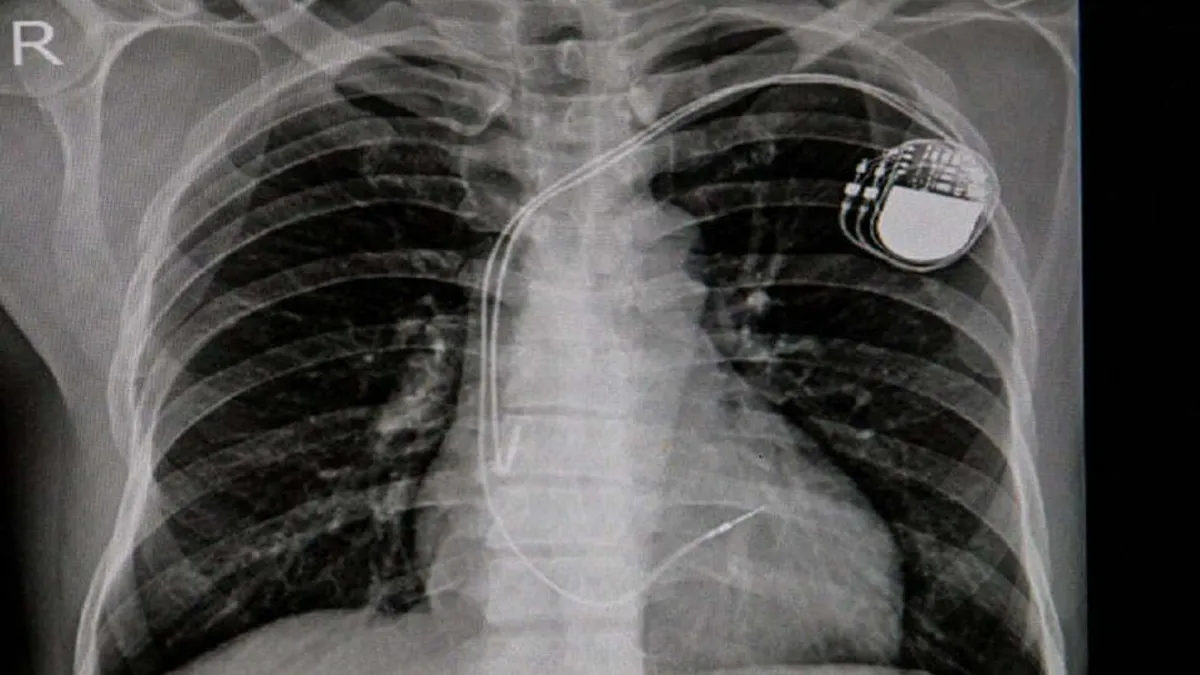

Stimulatoarele cardiace din cadavre, invenție germană (sursa: imperial.nhs.uk)